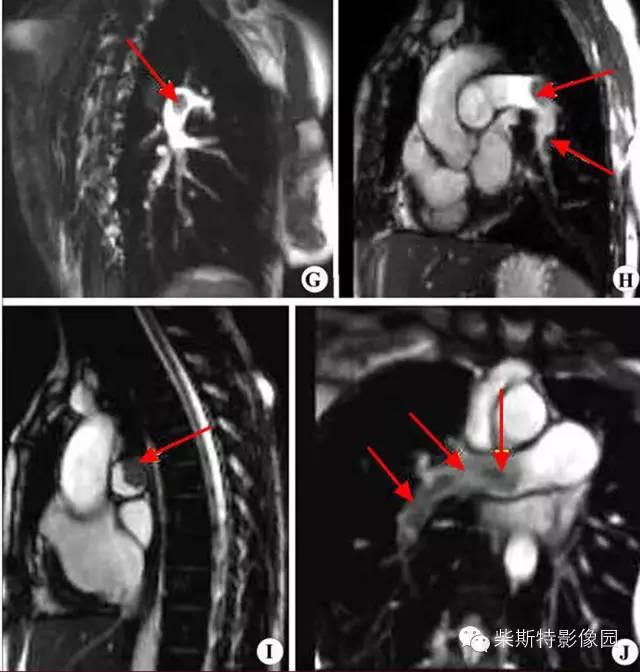

第三大名捕:肺动脉MRA

磁共振肺灌注成像(MRPP)

小编解析:

其实就论本领而言,肺动脉MRA与肺动脉CTA不相上下,二者各有千秋!只因肺动脉CTA速度上较其更快一些,故排名第二!